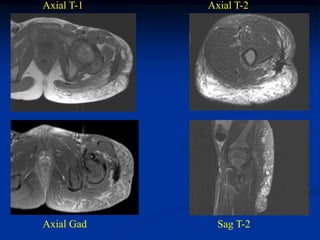

CLASSIC     Case #285         Sagittal T-1 MRI

67 year female with myxoid liposarcoma knee

Sagittal T-2 MRI

Axial T-2 MRI

Resection specimen

Photomic showing lipoblasts and vascular channels

CLASSIC Case #285 Sagittal T-1 MRI 67 year female with myxoid liposarcoma knee